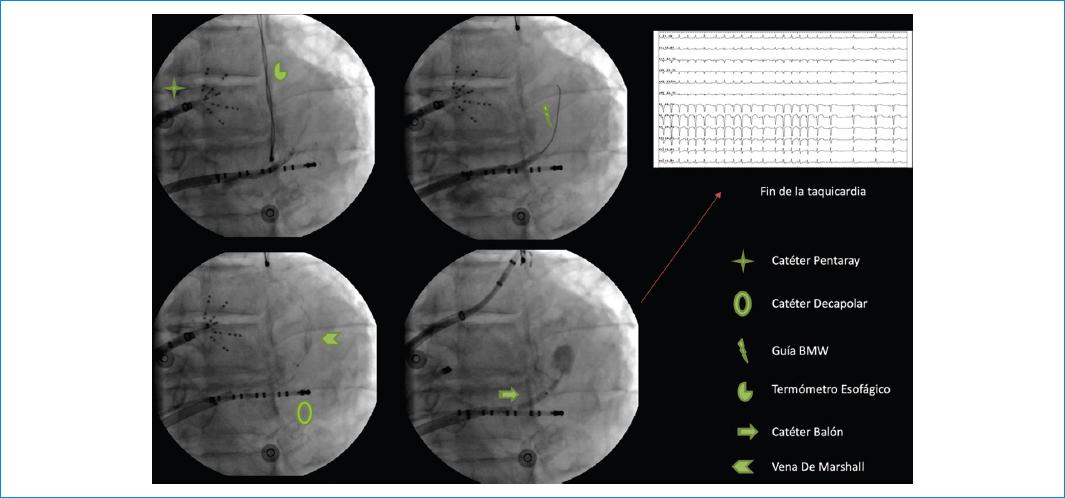

Figura 2 Secuencia de identificación, canulación, oclusión de vena de Marshall con catéter balón (5 atmósferas) e infusión de alcohol absoluto en 1 a 2 minutos, con una dosis total de 7.5 ml. En la parte superior derecha, el electrocardiograma evidencia la terminación de la taquicardia.